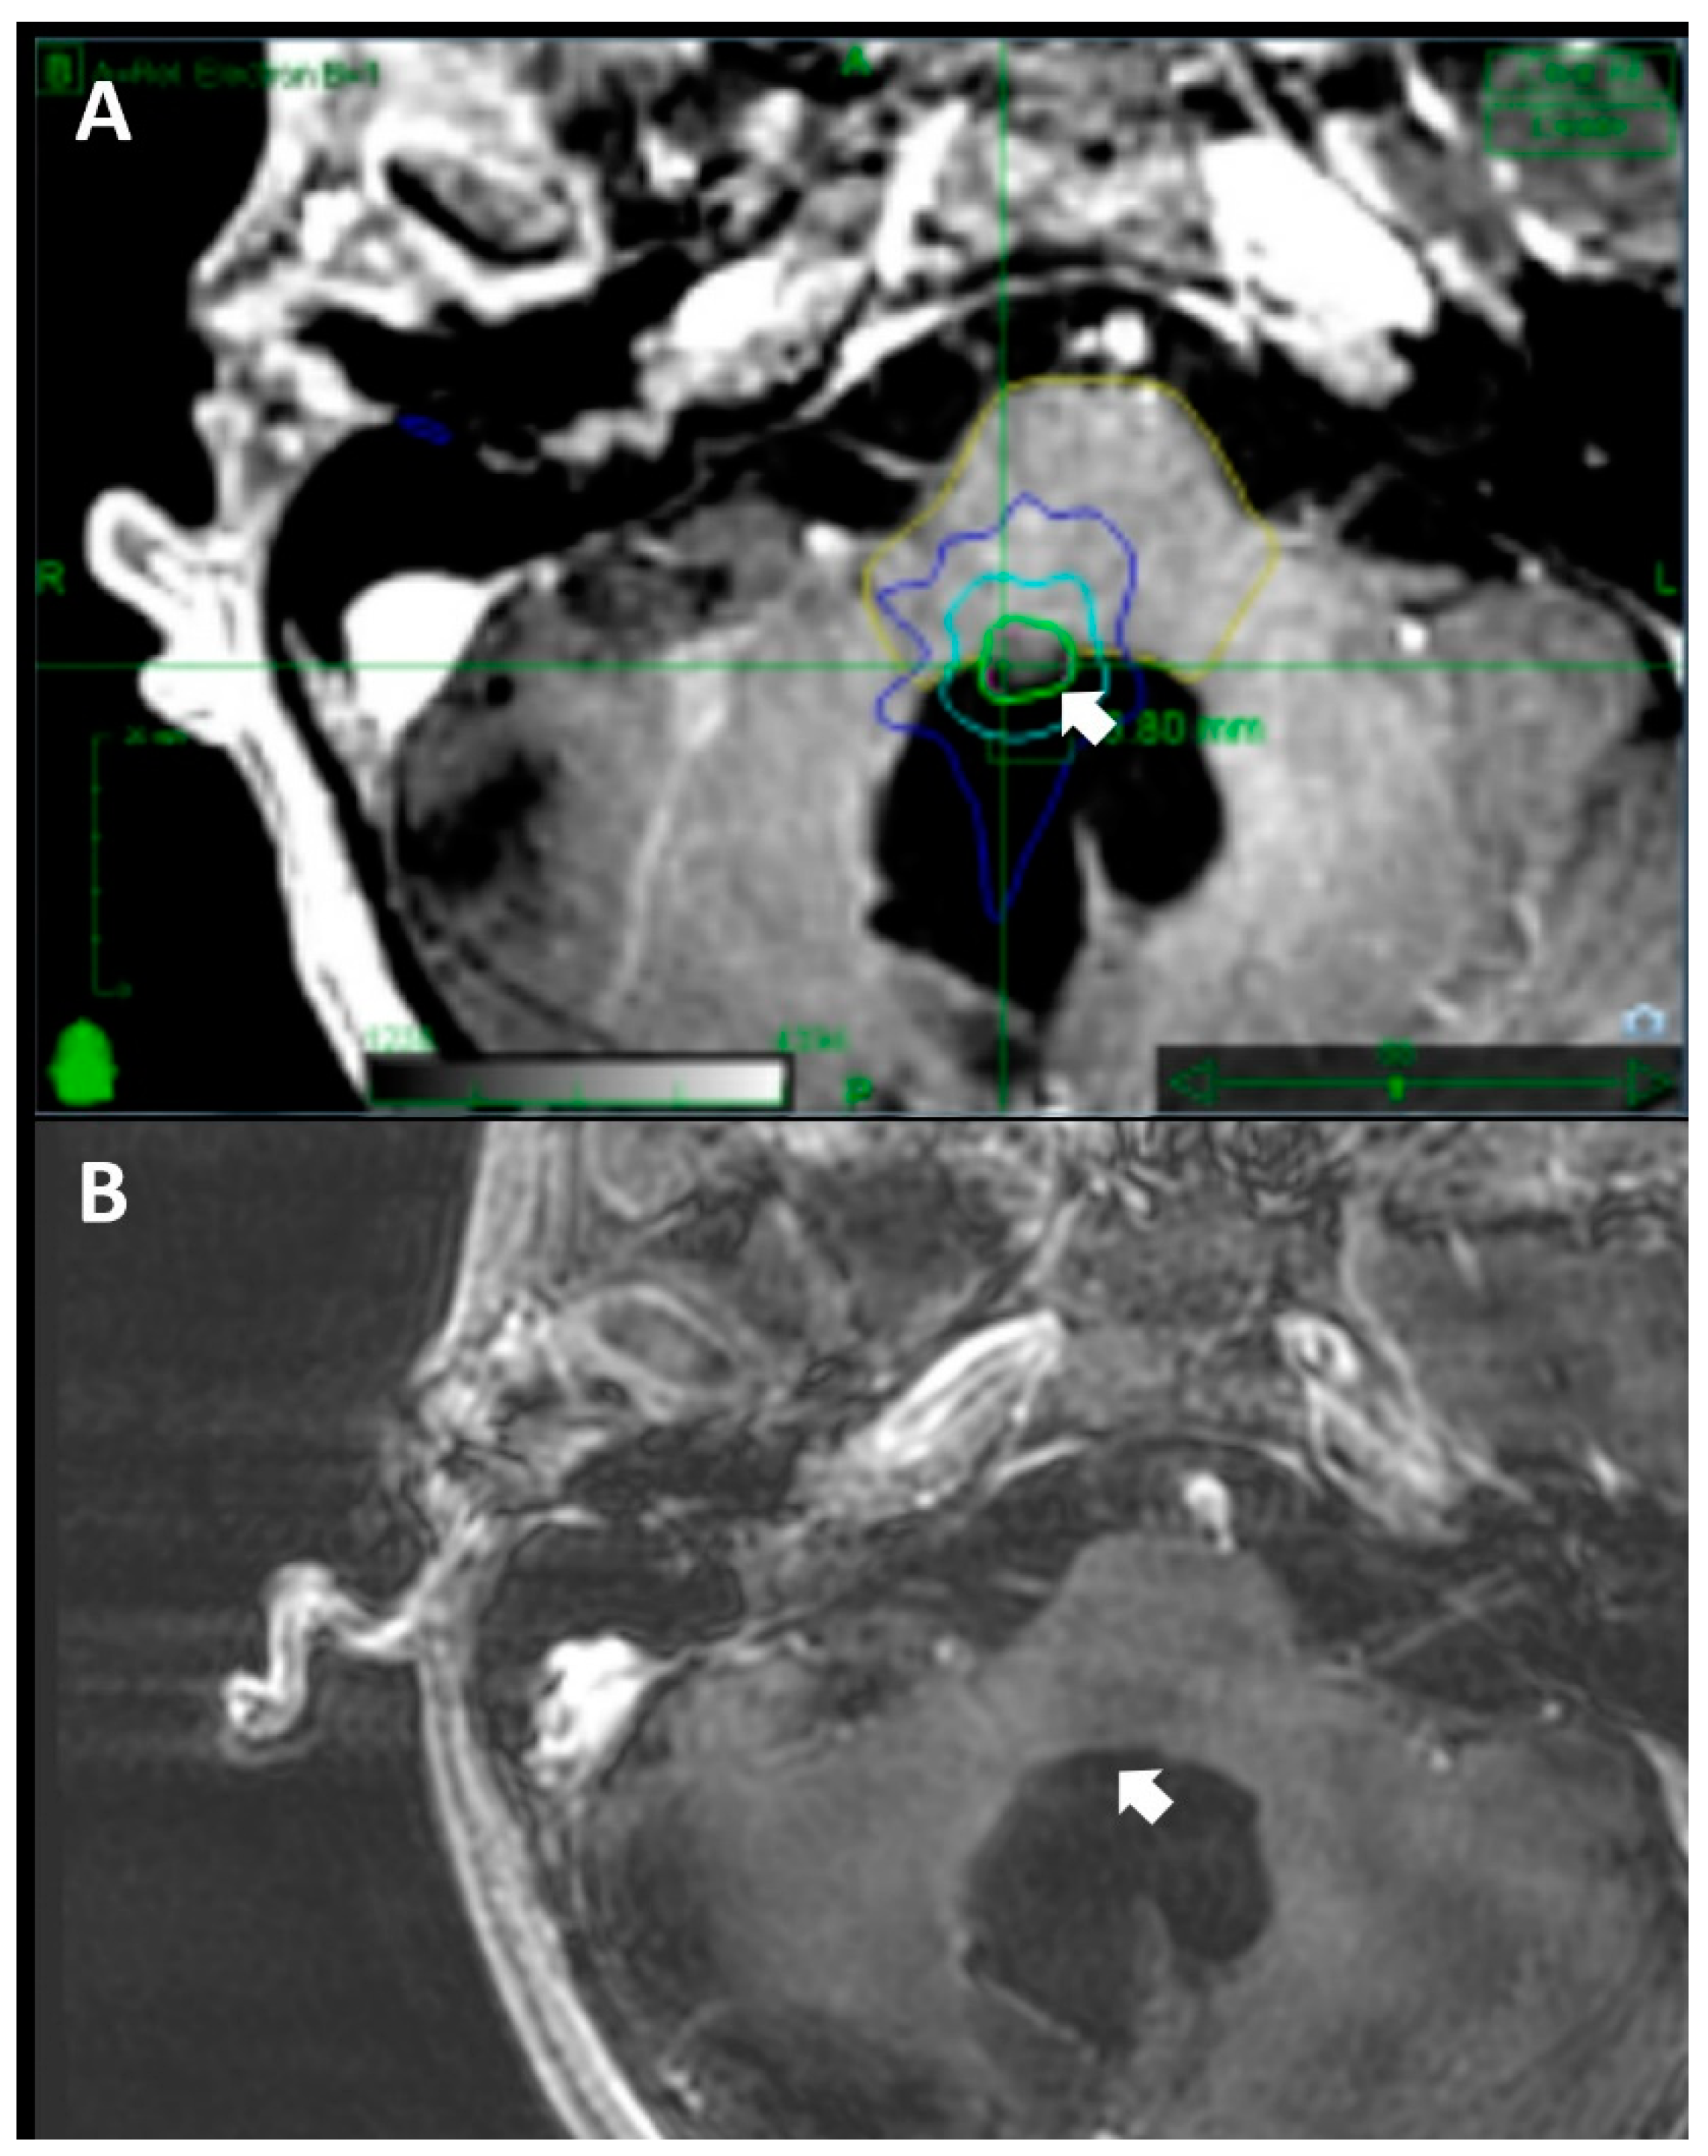

2.3. Treatment